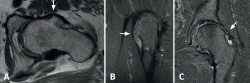

Figure 2. A and B: magnetic resonance imaging (MRI) axial view in T1 sequence (A) and coronal view in T2 sequence (B), revealing a large exostosis on the anterolateral surface of the femoral neck; C: coronal view in T2 sequence showing exostosis of the femoral neck and signs consistent with anterosuperior labral rupture.